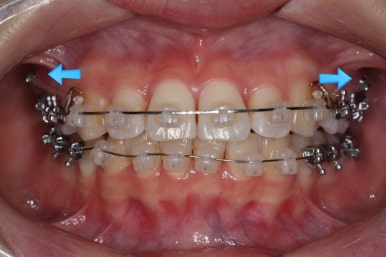

우선 윗니부터 가지런하게 합니다. 그리고 아랫니는 가지런하게 할 준비를 하죠.

화살표에 보이는 부착물의 이름이 바이트터보 입니다.

깊게 맞물리는 앞니, 즉 과개교합을 개선하기 위해 일시적으로 이용하는 장치입니다.

굉장히 효율적으로 과개교합을 개선할 수 있습니다.

아랫니에도 이제 장치를 붙였습니다.

과개교합인 채로 아랫니에도 장치를 붙이게 되면 아랫니 장치가 깨물려서 다 떨어지거나 부서지기 쉽습니다. 따라서 바이트터보는 굉장한 역할을 하게 됩니다.

눈으로 보기에는 과개교합이 개선이 된 것처럼 보이지만 아직은 아닙니다. 바이트터보가 남아있는 채로도 어금니가 맞물려야 진짜로 개선된 것이죠.